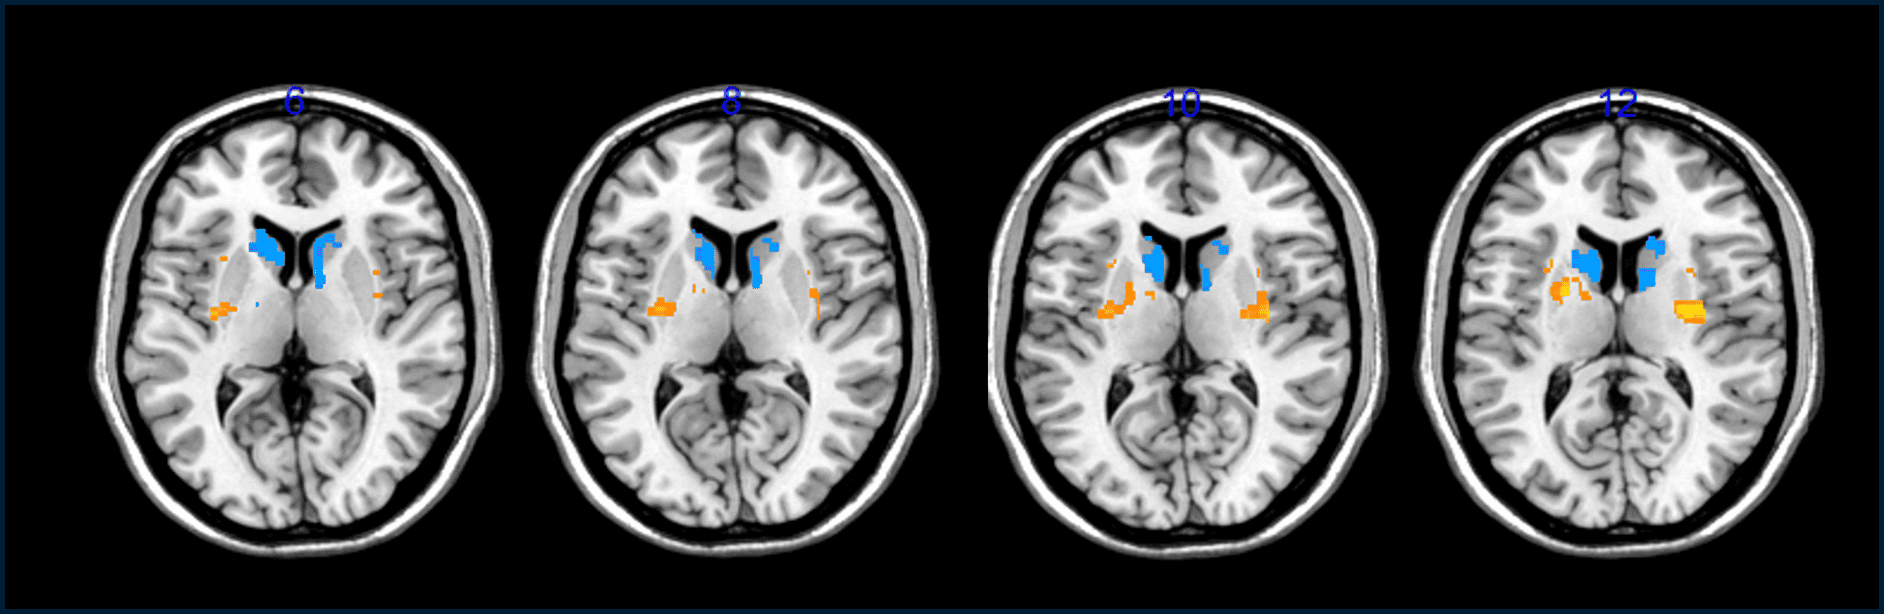

استُخلصت هذه المؤشرات التي تبيّن أن عمليات الزرع كانت مفيدة من عمليات مسح الدماغ التي بيّنت زيادة في عدد الخلايا التي تفرز الدوبامين في أدمغة المرضى وانخفاضاً في "فترة العجز"؛ وهي عدد الساعات اليومية التي يشعر فيها المتطوعون بأنهم عاجزون بسبب الأعراض التي يعانونها.

يتحقق الباحثون من بقاء الخلايا المزروعة على قيد الحياة من خلال حقن مادة مشعة سلف للدوبامين ثم مراقبة معدل امتصاصها في أدمغتهم باستخدام ماسح التصوير المقطعي بالإصدار البوزيتروني؛ وذلك لأنهم لا يستطيعون رؤية هذه الخلايا مباشرة بمجرد زرعها في أدمغة المرضى. بالنسبة إلى باركر؛ لم تكن هذه النتائج رصينة للغاية، وهو يقول إنه "ما يزال من السابق لأوانه معرفة" ما إذا كانت الخلايا المزروعة نجحت في ترميم التلف في أدمغة المرضى.